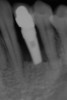

A 28-year-old Caucasian female presented to the periodontist with a complaint of a mobile implant in the site of tooth No. 22 (Figure 2 and Figure 3). The patient had a congenitally missing tooth No. 23. No. 22 had erupted into site No. 23, leaving a vacancy at site No. 22, and was the reason for the original implant at site No. 22.

The patient had no medical concerns and had a history of an implant placement in December 2002 when she was 25 years old. In February 2005, she presented with a mobile implant and an associated advanced peri-implantitis. Radiographic review at the initial examination demonstrated significant destruction of the dentoalveolar ridge around the implant as well as around the adjacent natural dentition. Emergency-based treatment involved surgical implant removal only and debridement of the infection (Figure 4 and Figure 5). Following uneventful healing, an advanced ridge defect was apparent at the edentulous site and moderate and advanced attachment loss noted at No. 22D and No. 21M, respectively (Figure 6 and Figure 7). This case demonstrates bone loss of two separate origins: lack of bone because of tooth agenesis and destruction of bone from inflammatory peri-implantitis.